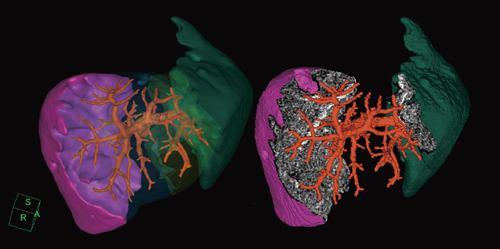

当社では,腹部ダイナミック造影データから肝臓実質を自動抽出する技術を開発し,門脈や静脈などから,脈管が持つ血管支配領域を計算するソフトウェアを,いち早く市場に投入した。肝臓解析を行う目的は,肝移植や肝切除の際に,切除部分の体積が肝臓全体に対してどれくらいか,残肝はどれくらいの容積であるかを術前に調べることにある。肝臓解析ソフトウェアにて切除体積を計算することによって,手術が肝臓に及ぼすダメージを推測でき,予後の判定に役立てることができる。また,体積計算だけでなく,ポリゴン表示やカット断面にグレイスケールの信号値を当てはめて表示する(図1)などの工夫を施すことで,臨床医にとって術中に注目される脈管の箇所を,よりイメージしやすいように開発されている。